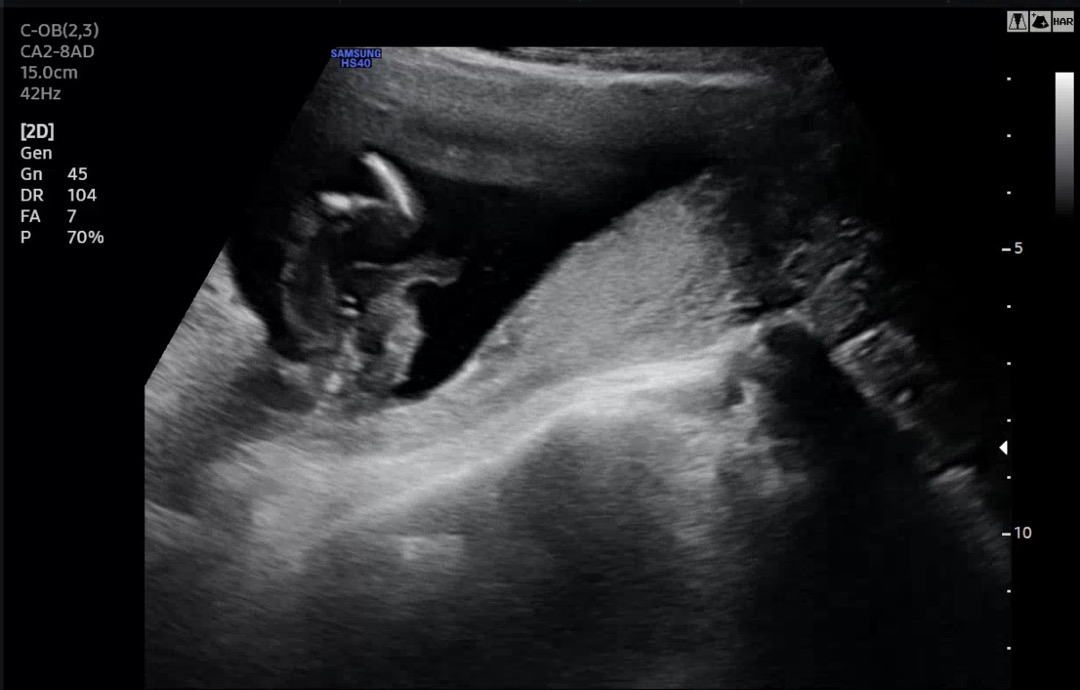

15주차 성별 반전 봐주세요ㅠㅠ

오늘 의사 선생님이 다리 사이에 뭐가 보인다고 아들이라고 생각하고 있으면 될것같은데 100프로는 아니다 라고 하셨는데 혹시 성별 반전 있을까요??

왕자님 한표요

저도 그랬는데 90퍼의 확률로 왕자래요 ㅎㅎ.. 남아는 거의 안바뀌더라구요